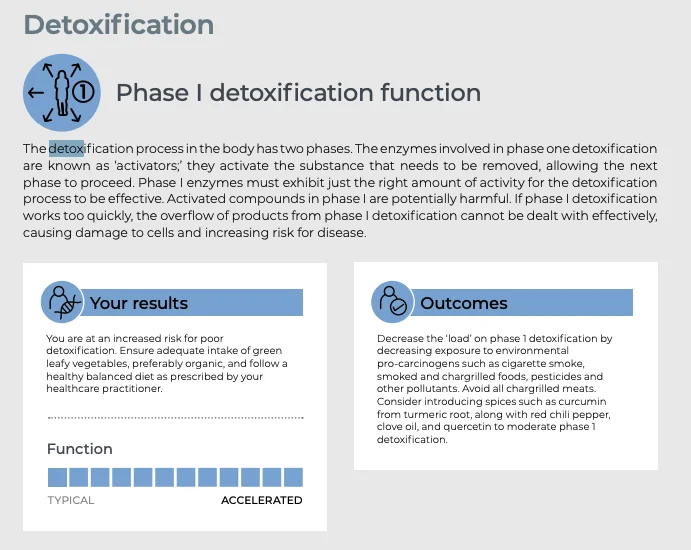

Detox & Half-Life Hangover

Common PED Adverse Effects

Prolonged drug effects causing insomnia, anxiety; buildup leading to dependency cycles.

Your Genetic Edge Tests That Matter

CYP3A4*22 (Drug Clearance), UGT2B17 (Drug Excretion)